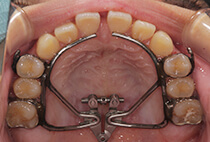

急速拡大装置、上顎前方けん引装置、コルチコトミー

診断の結果は、以下が原因の骨格性反対咬合。

反対咬合でよくあるケースです。

治療方法は、小さな上顎の成長誘導。

急速拡大装置と前方けん引装置を使用します。

成長のピークに合わせて上顎をもう一度拡大し、前歯のかみ合わせをさらに安定化。